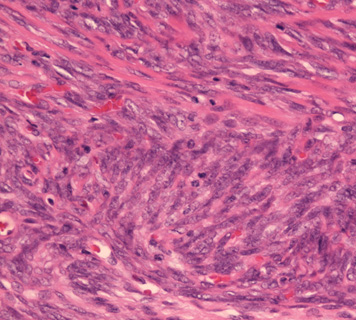

組織型

1. biphagic type; 古典的なタイプでさまざまな割合で明らかな上皮成分と紡錘細胞が混在する。

2. monophagic fibrous type; 線維肉腫様の紡錘細胞のみが増殖し上皮様細胞はみられない。

3. poorly differentiated type; 分化の低い類円形細胞肉腫でpericytomatous patternをとる。

biphasic type, monophasic typeは同じくらいの頻度で出現する。後者では免疫染色で上皮様分化をしめすこと, 特徴的な遺伝子異常を検出することが診断に必要となる。理論的にはmonophagic epithelial typeもあるが形態のみで診断は不可能。わずかな線維肉腫様成分をさがすことが診断にむすびつき, cytogenetic dataにより確診にいたる。

滑膜肉腫の最大の特徴は類上皮肉腫とならび代表的な上皮様分化を示す組織像にある。

腫瘍細胞の上皮的性格については電顕で上皮成分に基底膜形成や接着斑がみられること, 免疫染色で種々の分子量のcytokeratinやEMAの発現が認められることより真の上皮への分化と考えられている*18